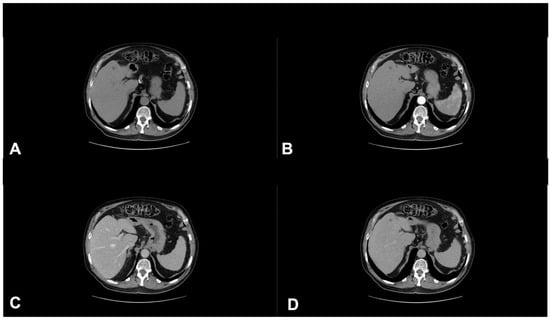

- Granata, V.; Fusco, R.; Filice, S.; Catalano, O.; Piccirillo, M.; Palaia, R.; Izzo, F.; Petrillo, A. The current role and future prospectives of functional parameters by diffusion weighted imaging in the assessment of histologic grade of HCC. Infect. Agents Cancer 2018, 13, 23. [Google Scholar] [CrossRef] [PubMed]

- Granata, V.; Fusco, R.; Avallone, A.; Filice, F.; Tatangelo, F.; Piccirillo, M.; Grassi, R.; Izzo, F.; Petrillo, A. Critical analysis of the major and ancillary imaging features of LI-RADS on 127 proven HCCs evaluated with functional and morphological MRI: Lights and shadows. Oncotarget 2017, 8, 51224–51237. [Google Scholar] [CrossRef]